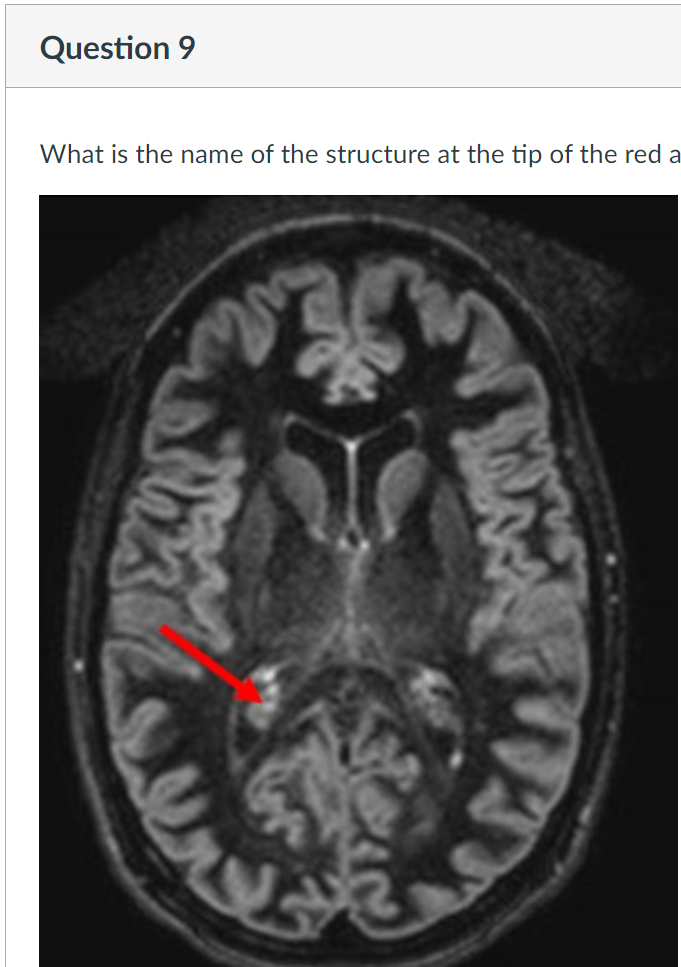

9

Q

A

insula

insular lobe